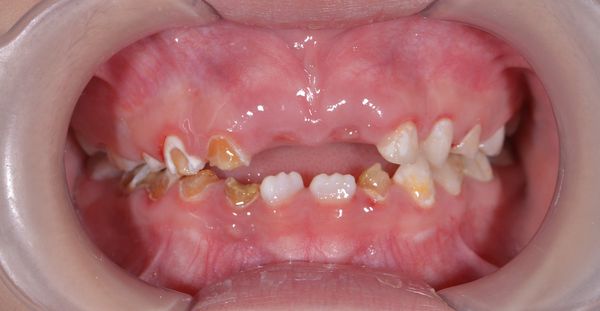

Đây là trường hợp bé 7 tuổi tới khám, bé bị sâu răng do bú bình từ nhỏ nhưng không được điều trị. Sau khi thăm khám bác sĩ đánh gía và đưa ra kế hoạch điều trị cụ thể như sau:

2. Sâu răng sớm hai hàm : mất men răng, mất mũi rãnh và hình dáng nên việc nhai thức ăn bị kém. Điều trị: trám và phục hồi với mão kim loại cho trẻ em.